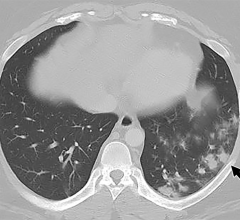

News | Coronavirus (COVID-19)

March 29, 2022 — Some people recovering from COVID-19 pneumonia have CT evidence of damage to their lungs that persists…

March 23, 2022 — Disease of the small airways in the lungs is a potential long-lasting effect of COVID-19, according to…